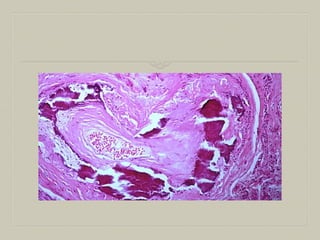

CASEOUS NECROSIS

 It is found in the centre of tuberculous foci

 It combines features of both coagulative ana liquefactive

necrosis.

GROSS :The necrotic areas appear dry,

cheesy, soft and yellowish

Microscopy :The necrosed foci are

structureless ,granular eosinophilic

The surrounding tissue shows chacteristic

granulomatous

reaction

 3)caseous necrosis---tuberculous infection.

 Gross—resembles cheese are soft granular

&yellowish

 Microscopy--

 Focus is structureless eosinophilic, contains

granular debris. granulomatus inflammatory

reaction with epitheloid cells, langhans giant

cells.or forein body giant cells. peripheral

mantle of lymphocytes.